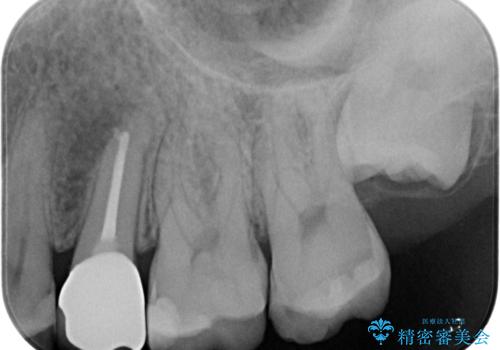

根管内の感染源を可能な限り除去し洗浄しました。

術後は腫れがなくなり特に症状も出ず、メンテナンスに移行しました。

- 左上5:再根管治療(リトリートメント・小臼歯)/121,000円、土台(ファイバーコア)/22,000円、仮歯/11,000円、ジルコニアクラウン(スタンダード)/121,000円 合計275,000円(税込)費用は治療当時の料金となります